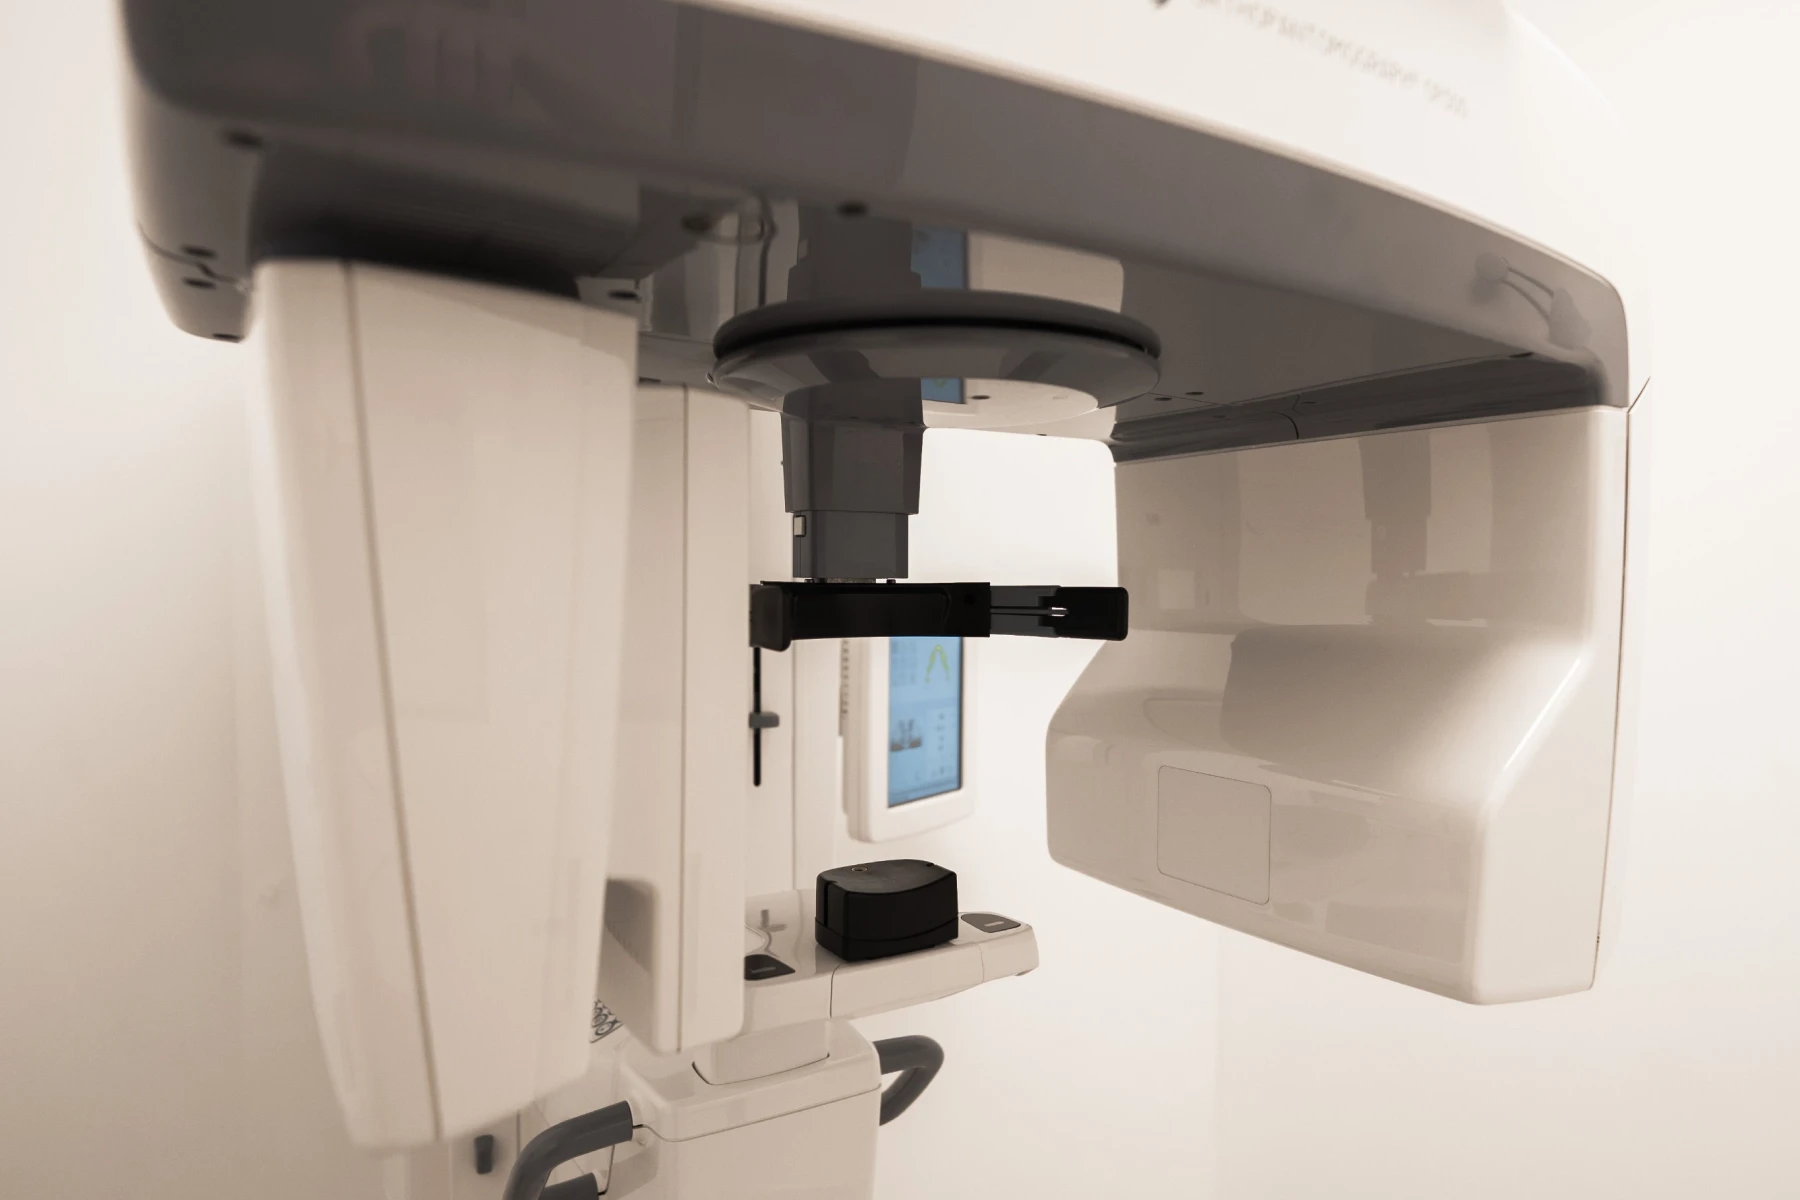

Radio panoramique 3D

La radio panoramique est une technologie permettant l’exploration précise des structures osseuses et dentaires en trois dimensions. Une technologie essentielle dans l’élaboration d’un plan de traitement et pour le suivi de chaque patient.